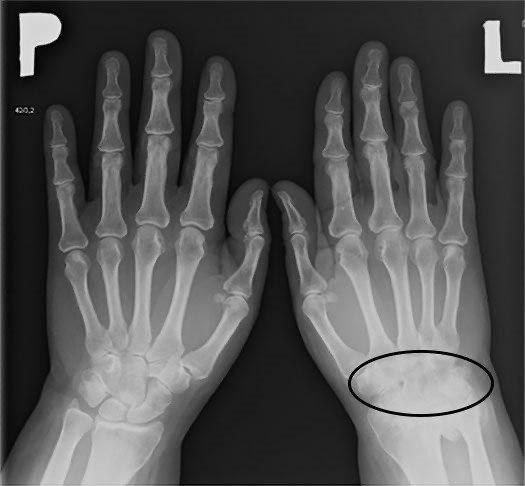

• Рентгенография — позволяет оценить сращение костей;

• МРТ и КТ — информативны при фиброзных анкилозах и ранних стадиях;